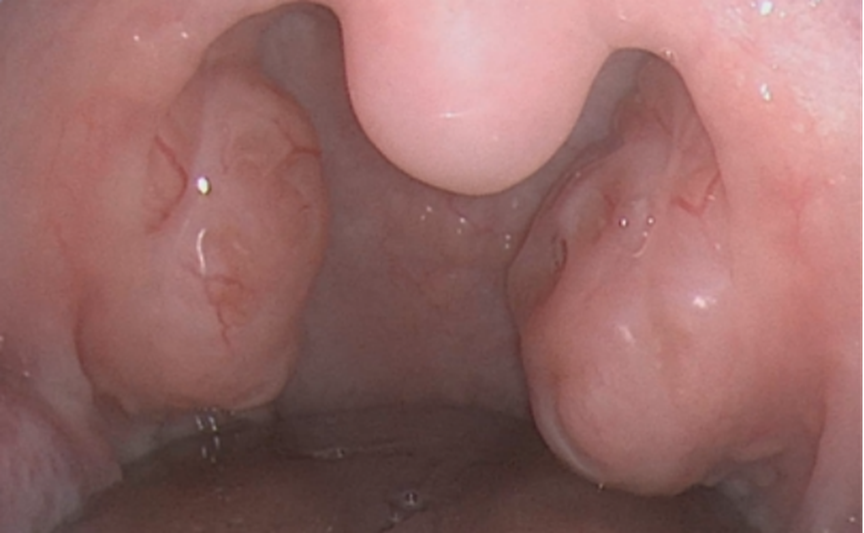

双侧扁桃体肿大

l 扁桃体过度肥大,导致睡眠呼吸暂停(睡眠打鼾、呼吸暂停),甚至影响正常吞咽和进食。